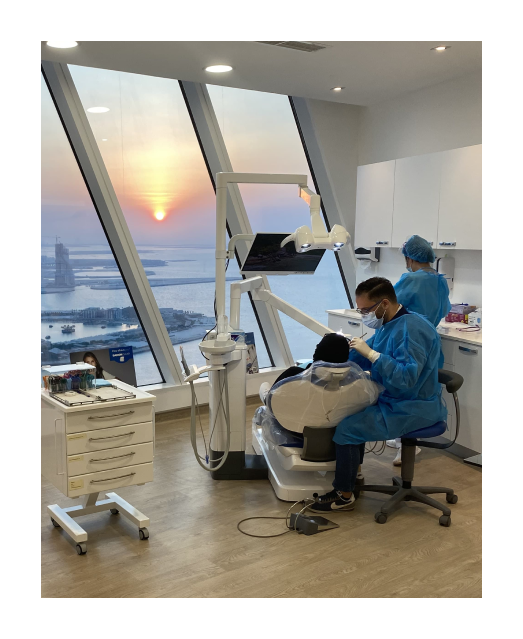

ONLY ONE KIND OF TREATEMENT

Your New Smile

Transforming Dental Care for a Brighter Tomorrow

Welcome to Dental Center

We believe that a healthy smile is a happy smile. Our dedicated team is committed to providing top-notch dental care in a friendly and comfortable environment. With years of experience and the latest technology, we ensure that every visit is tailored to meet your individual needs.

Why Choose Us

Specialists and Excellent Staff

State-of-the-art Technologies

Affordable Costs

Luxurious Environment